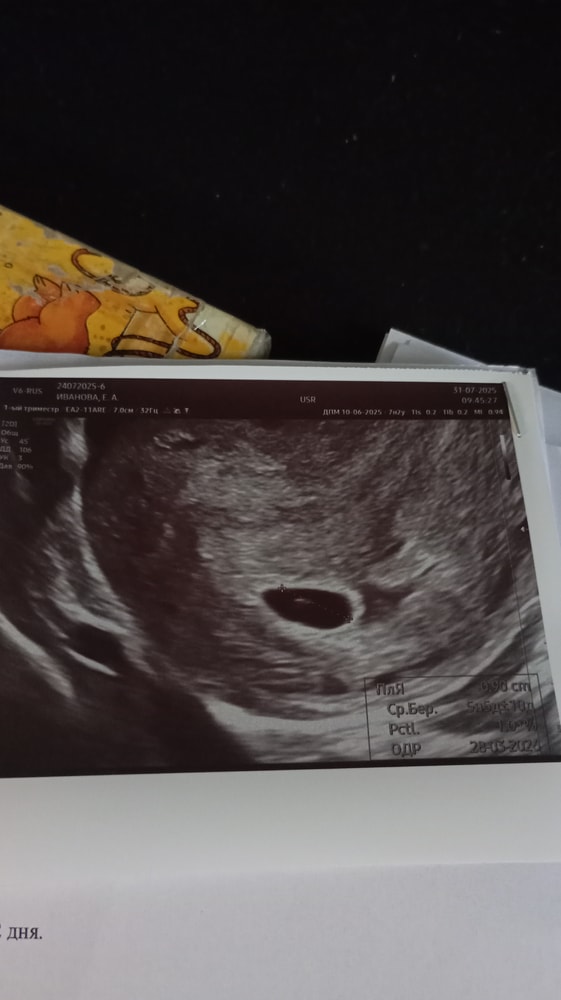

2е УЗИ от 31го - ПЯ 9мм, ЖМ 3.8, эмбриональный бугорок 2.5. срок по узи 5.5